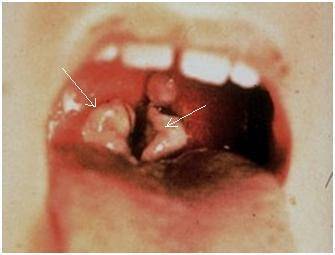

При непосредственном осмотре области миндалин визуализируется пленка беловато-желтовато-серого цвета. По внешнему виду она напоминает пятно от стеариновой свечки округлой формы. Пленка мягкая (по консистенции), окружена воспалительным (красным, отечным) ободком по краю и легко снимается ватным тампоном, после чего на его месте остается изъязвленная поверхность желтоватого цвета с ровными четкими контурами, которая кровоточит.

На первых порах заболевания язвенная ангина поверхностная. Но в случае длительного течения заболевания, дефект в тканях становится глубоким, приобретает кратерообразную форму, распространяется за пределы миндалины, вовлекая глубокие ткани. Иногда в патологический процесс вовлекается слизистая оболочка десен, язык и даже надкостница.

Для пораженной миндалины характерно увеличение в размерах. Она покрывается серовато — желтым налетом с дурным запахом. Его легко можно убрать медицинским шпателем. Симптомы гнойно воспалительного поражения проходят за 2 недели.

Гнойно воспалительный процесс часто затрагивает и соседние ткани полости рта и горла. Могут поражаться и слизистая щек и мягкое небо. Иногда болезнь протекает в сочетании со стоматитом.